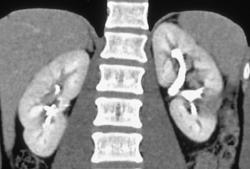

Renal Cell Carcinoma